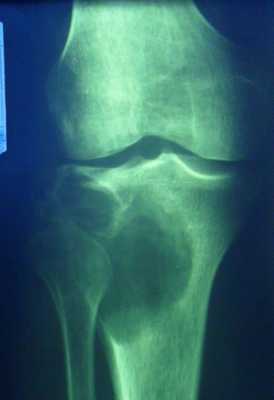

Гигантоклеточная опухоль

(остеобластокластома)

- состоит из клеток 2 типов- многоядерных гигантских и мелких одноядерных,

- поражаются люди в возрасте от 20 до 40 лет,

- локализация бедренная кость - дистальный конец, проксимальный конец б/берцовой кости, дистальный конец лучевой кости. Из плоских костей - тазовые кости и лопатка, очень редкая локализация в позвонках,

- одиночность и изолированность поражения,

- характерно расположение опухоли в эпиметафизраном отделе, который значительно вздут и деформирован, имеет вид крупнобугристого полушария, булавы,

- опухоль доходит до суставного хряща и обрывается,

- растет во всех направлениях, но главный рост происходит вдоль длинной оси кости в сторону с/3 диафиза кости,

- поперечник опухоли может увеличивать нормальный диаметр опухоли в 3-5 раз.

- ячеистый тип - опухоль состоит из отдельных камер, отделенных друг от друга полными и неполными перегородками (мыльные пузыри или неправильные соты),

- корковое вещество раздвигается, вздувается изнутри, истончается, надкостничных наслоений нет,

- при больших опухолях корковое вещество рассасывается и опухоль окружена со всех сторон тонкой скорлупой состоящая из стенок поверхностно расположенных ячеек.

- остеолитический тип - полное отсутствие ячеистого или трабекулярного рисунка, дефект кости вполне гомогенен,

- краевой блюдцеобразный дефект,

- корковый слой на пораженном месте рассасывается, а на границе с дефектом корка заострена, не подрыта и не имеет никаких периостальных наслоений,

- контуры дефекта резкие,

- патологические переломы в 12% случаев.